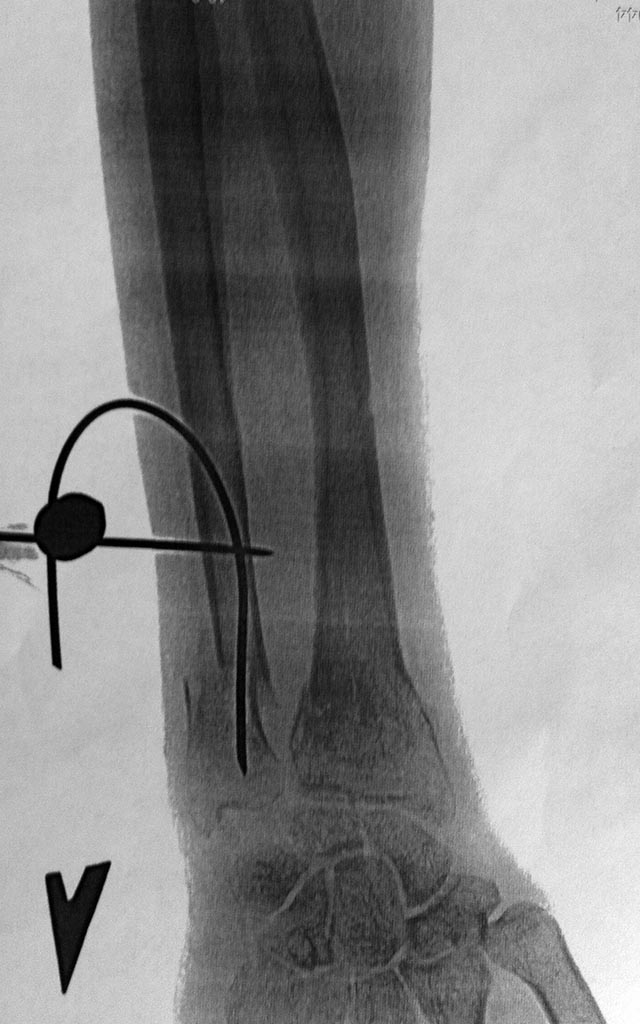

Здравствуйте, уважаемые коллеги! Хочу выложить окончательный результат

остеосинтеза, произведенного и выложенного мной на форум в июле этого года.

Как я уже говорил, пациент крайний недотрога и мое желание вести этого

пациента без иммобилизации не увенчалось успехом. В гипсе он проходил 4

недели. И оправдания мои худшие тоже оправдались - спицы лучевой кости

утянули в свою сторону спицу в локтевой, тем самым связующий узел с

локт. стороны уперся в головку. Благо, что пациент был у меня под

контролем и через 3 недели я удалил лучевые фиксаторы. Дальше уже все

"устаканилось" и пару дней назад я удалил оставшуюся конструкцию.